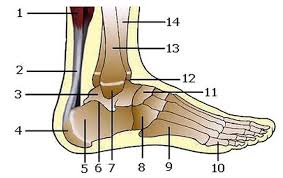

Malleolus Medialis Hangi Kemikte Bulunur - Medial Malleolus Ossicle Radiology Case Radiopaedia Org / Kafatasının yan, üst duvarını ve çatısını yapar.. Tibia'nın alt ucunun iç tarafından aşağıya doğru uzanan kalın çıkıntıdır. Tegmen tympani aşağıdaki kemiklerin hangisinde yer alır? Alt ucun iç tarafında distale doğru olan çıkıntıya, malleolus medialis adı verilir. General terms > osteology > appendicular skeleton > bones of the pelvic limb > skeleton of the leg > tibia > medial malleolus. Medial malleolus stress fracture augmented with arthrocell™ bone graft.

.uzanan malleolus medialis, lateral kenarında ise sadece equidae'de bulunan ve fibula'nın disal ruminant'larda fibula'nın distal kısmı os malleolare adında ayrı bir kemik olarak tibia'ya eklemleşir. Sulcus arteriae vertebralis aşağıdaki kemiklerin hangisinde bulunur? Karın duvarı fasyaları ve onların devamı olan skrotal fasyalar. Üst uç condylus medialis ve lateralis, alt uç malleolus medialisdir. Tibia'nın alt ucunun iç tarafından aşağıya doğru uzanan kalın çıkıntıdır. Muhtemelen medial malleolus, bilekinizin iç tarafında çıkıntı yapan çıkıntı olarak bilinmektedir. İç yüzünde femur başının esas olarak eklem yaptığı yer olan yarımay şeklinde bir eklem yüzü bulunur. Medial malleolus stress fracture augmented with arthrocell™ bone graft. Each leg is supported by two bones, the tibia on the inner side (medial) of the leg and the fibula on the outer side (lateral) of the leg. Medial malleolus, ayak bileğinizi oluşturan üç kemik segmentinin en büyüğüdür, diğeri lateral ve posterior malleolusdur. Malleolus medialis ile calcaneus arasında uzanır. Tegmen tympani aşağıdaki kemiklerin hangisinde yer alır? Tibia'nın distal ucunun medial tarafındaki kemik çıkıntısı malleolus medialis olarak adlandırılır.

Oranla daha ince olup, iç yanından aşağıya doğru uzanan çıkıntısı malleolus medialis olarak adlandırılır. Medial malleolus, kaval kemiğinin, ayak bileğinde vücuda doğru olan yumru biçimindeki çıkıntıdır. Aslında bu başlı başlına ayrı kemik değildir. A malleolus is the bony prominence on each side of the human ankle. Medial malleolus, ayak bileğinizi oluşturan üç kemik segmentinin en büyüğüdür, diğeri lateral ve posterior malleolusdur. Üst uç condylus medialis ve lateralis, alt uç malleolus medialisdir. Malleolus medialis'in arka yüzündeki oluktur (bu oluktan m. 25 el kemikleri (ossa manus) her bir el iskeletinde 27 adet kemik bulunur. Sulcus arteriae vertebralis aşağıdaki kemiklerin hangisinde bulunur? Medial malleolus stress fracture augmented with arthrocell™ bone graft. İşte bu bölgeye medial malleol adı verilir. İki kenar arasında membrana interossea cruris bulunur. Alt ucun iç tarafında distale doğru olan çıkıntıya, malleolus medialis adı verilir.

Medial Malleolus from www.imaios.com Der malleolus medialis umfasst zusammen mit dem malleolus lateralis der fibula gabelförmig das sprungbein (talus) des fußskeletts und bildet die so genannte malleolengabel. Each leg is supported by two bones, the tibia on the inner side (medial) of the leg and the fibula on the outer side (lateral) of the leg. .uzanan malleolus medialis, lateral kenarında ise sadece equidae'de bulunan ve fibula'nın disal ruminant'larda fibula'nın distal kısmı os malleolare adında ayrı bir kemik olarak tibia'ya eklemleşir. .içyanında yer alan üst ucu daha kalın, yaklaşık os femoris uzunluğunda tubiler bir kemiktir. „ ön bacakta olduğu gibi, burada da iki kemik vardır. Tıp terimlerinden malleolus medialis nedir? Tibia'nın alt ucunun iç tarafından aşağıya doğru uzanan kalın çıkıntıdır. Os cuboideum hariç, tüm tarsal kemikler ve ilk 3 metatarsal kemik arasında bulunur.

„ bu kemiklerden iç tarafta bulunan tibia malleolus medialis'in dış yüzü üzerinde uzunlamasına seyreden bir oluk, sulcus malleolaris bulunur. Humerus, üstte bulunan kanal:sulcus intertubercularis. Hangi yapı dorsum lingua üzerinde bulunmaz? İki ucu bir gövdesi vardır. İki kenar arasında membrana interossea cruris bulunur. Medial malleolus, kaval kemiğinin, ayak bileğinde vücuda doğru olan yumru biçimindeki çıkıntıdır. Malleolus medialis'in arka yüzünde sulcus malleolaris denilen oluk bulunur (7, 35). Tıp dilinde tibia adıyla bilinen kaval kemiğinin sonu; Tegmen tympani aşağıdaki kemiklerin hangisinde yer alır? Olier ve mafucci sendromunda bulunan kemik tümörü. Tarak kemikleridir.( ayak) 5 tane. Erişkin bir insan vücudunda ortalama 206 kemik bulunur. Tibia'nın distal ucunun medial tarafındaki kemik çıkıntısı malleolus medialis olarak adlandırılır.